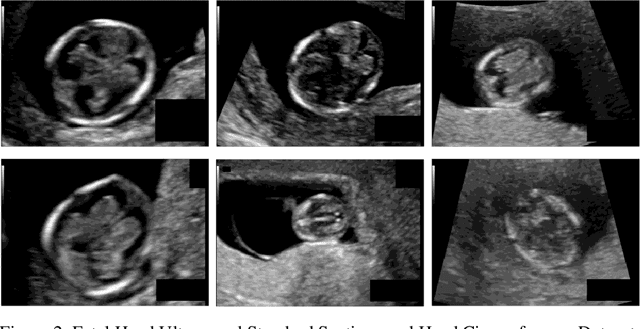

Abstract:Medical image segmentation, particularly in the context of ultrasound data, is a crucial aspect of computer vision and medical imaging. This paper delves into the complexities of uncertainty in the segmentation process, focusing on fetal head and femur ultrasound images. The proposed methodology involves extracting target contours and exploring techniques for precise parameter measurement. Uncertainty modeling methods are employed to enhance the training and testing processes of the segmentation network. The study reveals that the average absolute error in fetal head circumference measurement is 8.0833mm, with a relative error of 4.7347%. Similarly, the average absolute error in fetal femur measurement is 2.6163mm, with a relative error of 6.3336%. Uncertainty modeling experiments employing Test-Time Augmentation (TTA) demonstrate effective interpretability of data uncertainty on both datasets. This suggests that incorporating data uncertainty based on the TTA method can support clinical practitioners in making informed decisions and obtaining more reliable measurement results in practical clinical applications. The paper contributes to the advancement of ultrasound image segmentation, addressing critical challenges and improving the reliability of biometric measurements.